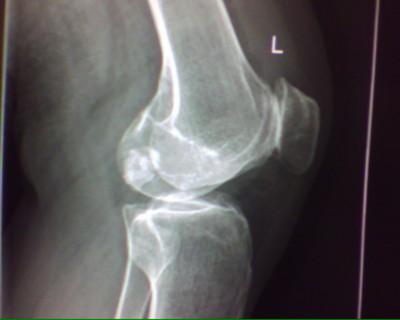

(图:患者治疗后左膝关节X线片)

到院检查后发现,薛女士四肢关节压痛明显,双膝关节异常红肿,超敏C反应蛋白高达97.5mg/L,诊断为风湿性关节炎中期。规范化治疗三个疗程后,关节疼痛肿胀消失,行动关节活动无声响,未见关节麻木现象,膝关节能够自由屈伸、下蹲、行走。超敏C反应蛋白降至4.3mg/L,类风湿因子18.5IU/ml,临床诊断风湿病症消除恢复健康。